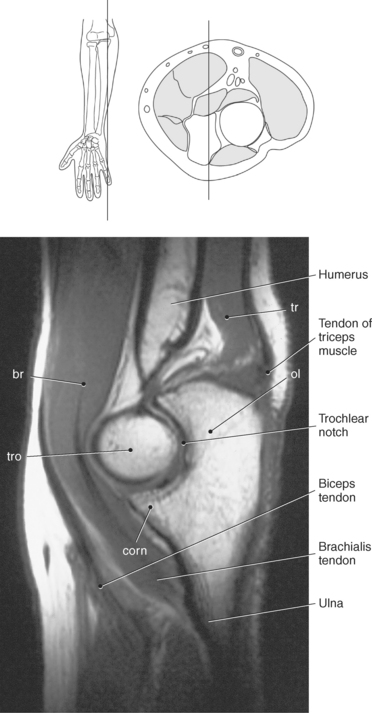

Figure 9.71 Coronal T1-weighted MR scan of elbow.

Key: ol, Olecranon fossa; me, medial epicondyle; tro, trochlea; le, lateral epicondyle; cap, capitellum; rh, radial head; rt, radial tuberosity; rn, radial notch; corn, coronoid process.

The distal portion of the humerus has two distinct prominences termed the medial and lateral condyles, with associated epicondyles, that provide attachment sites for tendons and ligaments (Figure 9.70). The medial epicondyle serves as the site of origin for the common flexor tendon, pronator teres muscle, and medial collateral ligament, whereas the lateral epicondyle serves as the attachment site for the common extensor tendon, supinator muscle, and lateral collateral ligament. Just lateral to the medial epicondyle along its posterior surface is a shallow groove containing the ulnar nerve. Two depressions located on the distal humerus are the anterior coronoid fossa and the deep posterior olecranon fossa. These depressions accommodate the coronoid and olecranon processes of the proximal ulna (Figures 9.70, 9.71, and 9.73). The distal humerus has two cartilage-covered articular surfaces—the capitellum and the trochlea for articulation with the radius and ulna (Figure 9.71). The lateral of the two surfaces is the capitellum, a rounded projection that articulates with the concave surface of the radial head. The trochlea is more medial and has the appearance of an hourglass if viewed in the horizontal plane. The shape of the trochlea helps keep the ulna in position during flexion between the distal humerus and proximal radius (Figure 9.73).

The ulna is located medial within the forearm. The proximal ulna consists of the olecranon and coronoid processes and the trochlear and radial notches. The superficial dorsal surface is formed by the hook-shaped olecranon process, which is the attachment site for the triceps brachii. The trochlear notch is a half-moon-shaped concave articular surface that curves around the trochlea of the humerus. This articulation allows for flexion and extension of the elbow. Located on the anterior portion of the distal end of the trochlear notch is a small beaklike process called the coronoid process. Just distal and lateral to the coronoid process is a flattened depression called the radial notch. It is covered by articular cartilage for articulation with the radial head. Immediately distal to the coronoid process is a roughened bony surface termed the ulnar tuberosity. The tendon of the brachialis muscle inserts on both the coronoid process and the ulnar tuberosity (Figures 9.72, 9.73, 9.75, and 9.76).